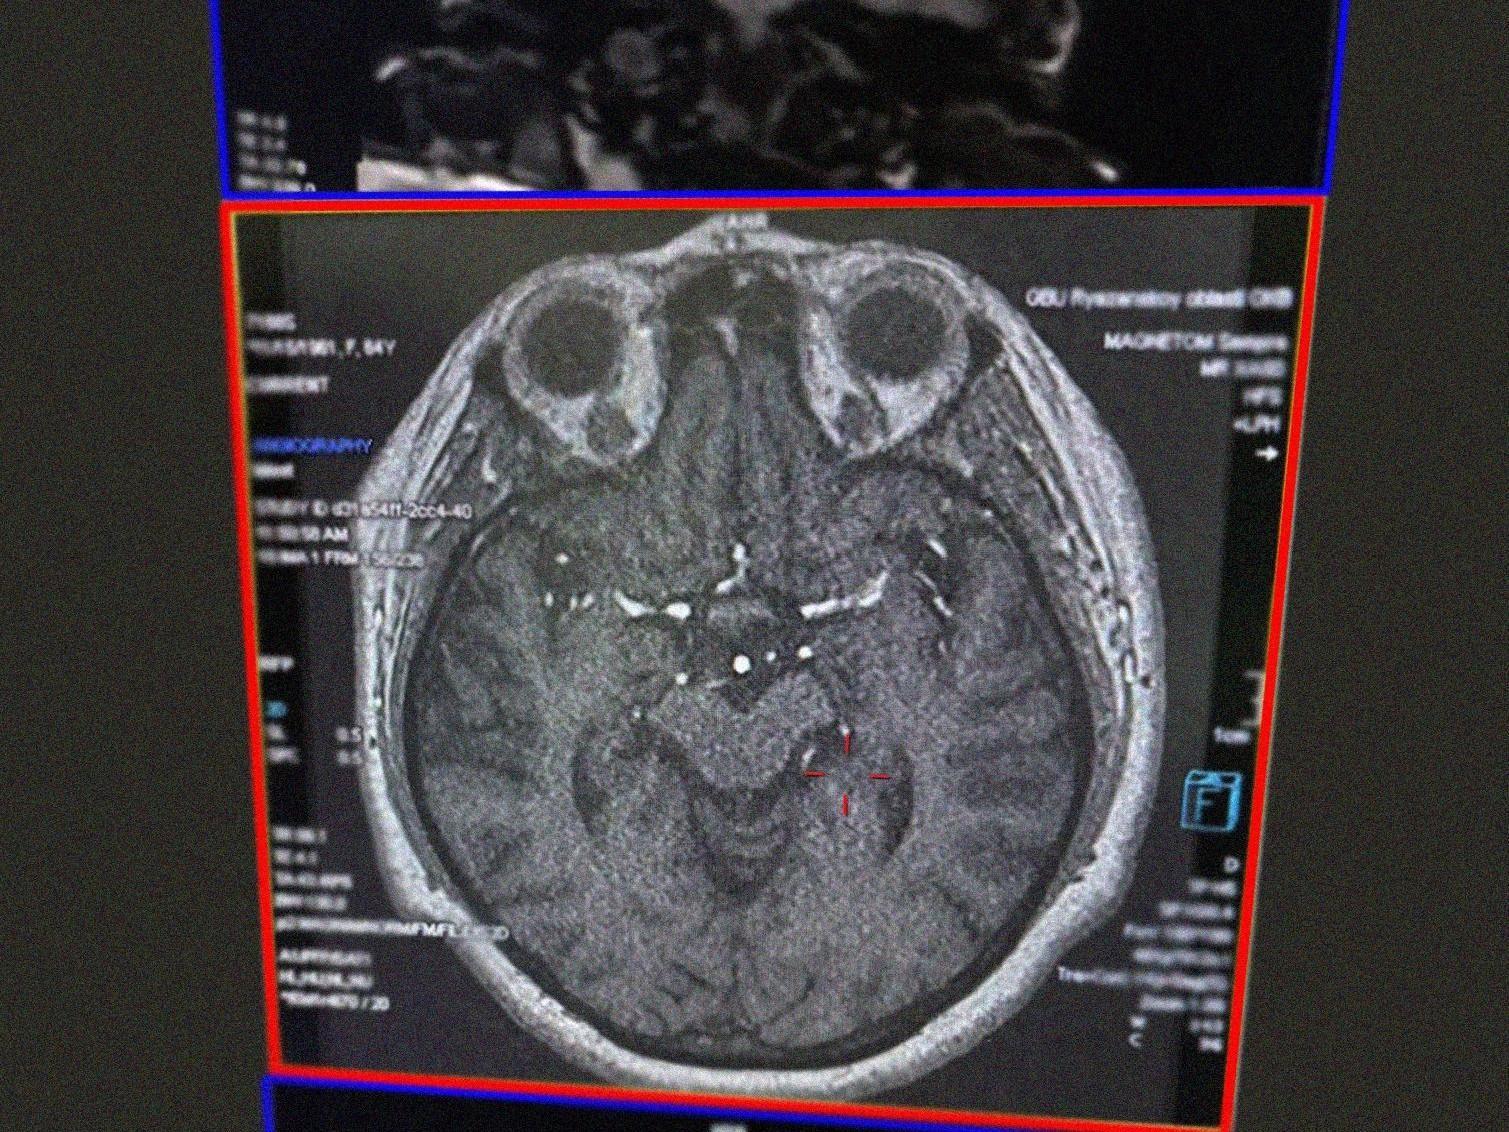

Doctors at the Ryazan Regional Clinical Hospital saved an 80-year-old woman who suffered a stroke. Her neighbor called the ambulance; they had planned to celebrate Christmas together, the regional Ministry of Health reported.

Doctors at the regional hospital confirmed the diagnosis and started preparing the elderly woman for thrombolysis.